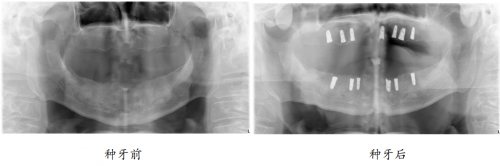

“口福行动”让80岁高龄老人缺牙重生

82岁的孙爷爷,10年前就已全口无牙,一直戴着活动假牙勉强吃饭。

近3年,活动假牙松动厉害,一吃东西就脱落,孙爷爷只能喝打成糊状的蔬菜和肉,“我看到这些,一点胃口都没有,肚子还空着,嘴里又吃不下,不知道是饿还是饱。总之吃饭好似‘上刑场’一样。”牙齿的缺失,让孙爷爷无比怀念老伴做的红烧肉,渴望重新拥有一口健全、有强劲咀嚼力的好牙,回到可以开怀大笑的日子。

偶然间,在社区举办的“修复失牙·口福行动”公益活动,实现了孙爷爷的种牙梦。

如今种牙1年后,孙叔叔的生活质量得到改善,一日三餐饮食结构丰富,红烧肉、苹果、坚果样样都能轻松消化,“多亏在‘修复失牙·口福行动’公益活动上遇见綦健院长,我现在精气神十足,邻居都说我年轻了10岁。”重获新牙的孙爷爷高兴道。

“在‘修复失牙·口福行动’公益活动中,有很多孙爷爷这样的患者。”北京维乐口腔綦健院长介绍:“牙齿就像公路上的汽车,启动需要能源,而牙齿就像汽车的发动机,源源不断给身体运转提供能源。汽车最终能走多远,就看能源有多少。同样的,齿龄=寿龄,老人拥有一口好牙,有助于食物消化,促进营养吸收,从而改善机体健康,延缓衰老,延长生命。维乐口腔举办‘修复失牙·口福行动’公益活动就是希望帮北京市民重拾口福,拥有健康的身体。”